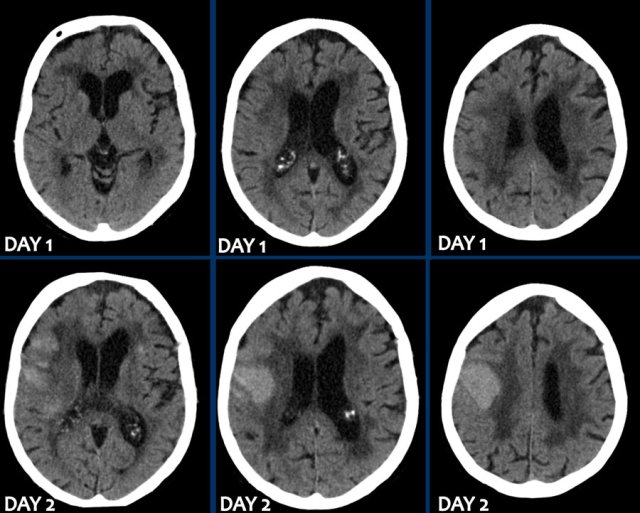

The first three images show a large hematoma in the basal ganglia on the right with massive edema.

The follow up image one year later shows  linear cavitation due to tissue loss (arrow) and hypodensity of the basal ganglia as a result of  gliosis.

The images show a hemorrhage in the basal ganglia in a patient with longstanding hypertension.

It is located in the head of the caudate nucleus.

The head of the caudate nucleus receives its blood supply from Heubner’s artery and the lenticulostriate arteries,.

A rupture in these arteries causes parenchymal hemorrhage.

The presence of an intraventricular haematoma is considered a poor prognostic factor due to the obstruction to CSF with hydrocephalus and raised intracranial pressure.